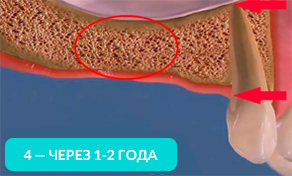

Отсутствие хотя бы одного зуба приводит к лавинообразной потери оставшихся.

Оставшиеся зубы начинают заполнять пустоты и смещаться.

На рисунке видно, какие щели между зубов образуются уже через год, после удаления.

Оставшиеся зубы смещаются в сторону и вытягиваются из десны. Зубам необходимо иметь опору (особенно при жевании). Если такой опоры нет, то они начинают ее искать и выдвигаться из десны.

Через год изменения уже будут видны невооруженным глазом. Выдвинутый зуб будет мешать при протезировании противоположного. Придется подпиливать выдвинувшийся зуб или возвращать его на место с помощью ортоимплантов.

На 4-ом рисунке видно, что костная ткань стала значительно тоньше, теперь в это место уже невозможно установить импланты (потребуется операция по наращиванию костной ткани).

Обратите внимание, насколько тоньше стала кость на рисунке 4, как постепенно обнажается корень оставшегося зуба.

Убыль костной ткани распространяется на соседние зубы и их корни постепенно обнажаются!

Зубы, расположенные рядом с местом удаления, со временем становятся нестабильными и могут быть утрачены.